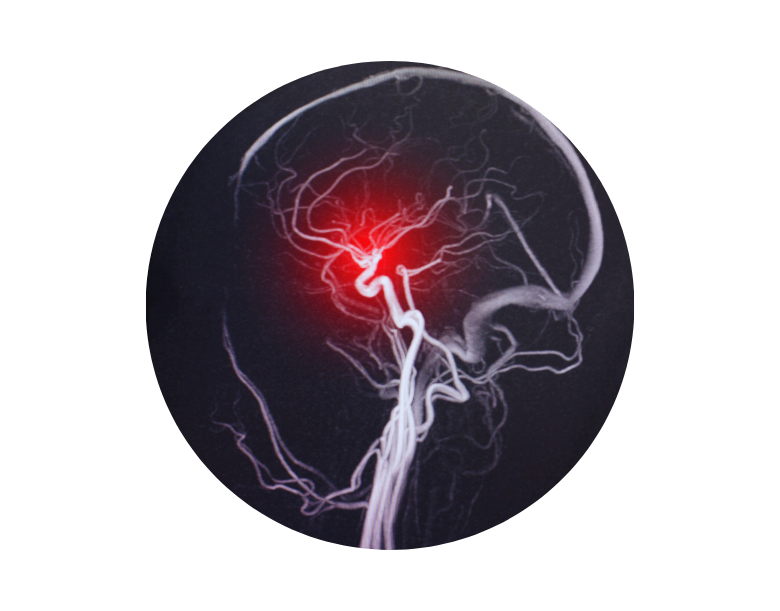

A brain haemorrhage is a serious health problem that can occur in three different anatomical areas: brain tissue, brain cavities and the surface of the brain. Cerebral haemorrhage can occur suddenly and unexpectedly, leading to serious disability or death. In this article, I will provide detailed information about the symptoms, types, diagnostic methods and treatment processes of brain haemorrhage. Since brain haemorrhages are conditions that usually develop rapidly and require urgent intervention, early recognition of symptoms is vital. A cerebral haemorrhage occurs when blood fills the brain tissue or cerebral membranes as a result of rupture or leakage of blood vessels in the brain. This can cause serious neurological damage by preventing the brain from performing its normal functions.